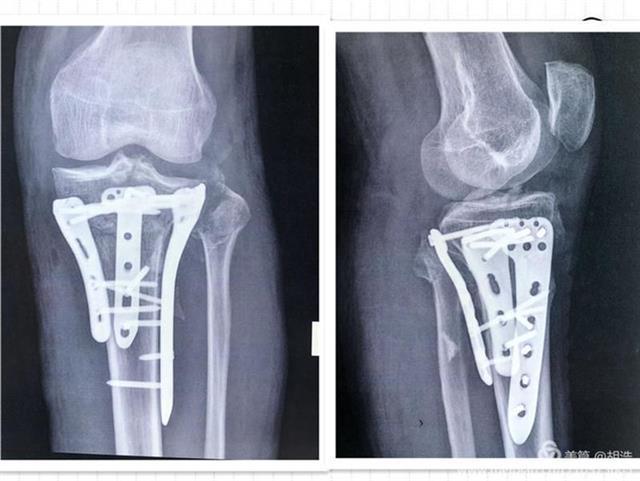

近日,协和江南医院/江夏区第一人民医院骨科创伤关节组,成功的为一位胫骨平台粉碎性骨折的患者实施了手术,这是该院骨科第二次成功将3D打印技术与传统的骨科手术结合取得的成果。

今年68岁的罗爹爹,因车祸导致头部、左膝部受伤,入院诊断:硬膜外血肿、左胫骨平台粉碎性骨折(SchatzkerⅥ型)、左腓骨小头骨折。考虑该患者年龄大,合并脑部损伤,骨折粉碎严重,为缩短手术时间、提高效率和手术质量,该院骨科主任杨俊忠提出了用3D打印技术辅助手术治疗,制定手术方案,精准治疗。

数字化设计结合3D打印技术,打印出了受损的胫骨、腓骨、股骨模型。在杨俊忠带领下骨科创伤关节专家组成员副主任医师胡浩、副主任熊家亭、医师黄攀、黄传文进行了术前的讨论,根据模型精准了解骨折类型,设计手术切口、预演术中步骤、内植物的安放位置及术中复位技巧,制定出可行的治疗方案,手术按照计划进行,术后的康复也令人满意。